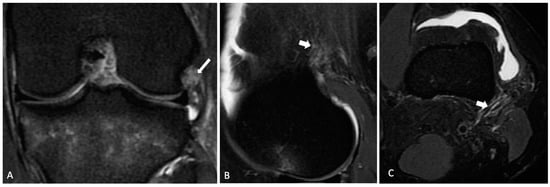

2.2. Radiological Analysis